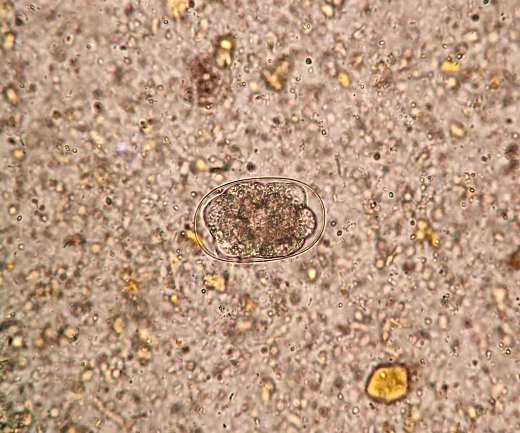

钩虫卵

钩虫卵椭圆形,(56-76)um x (36-40)um,无色透明,卵壳极薄,卵内通常含2

图为漂浮后的钩虫卵(40×10)▲图为漂浮后的受精蛔虫卵与钩虫卵(40

图2 低倍镜下(10x)手机放大版的三个钩虫卵,其中红色圆圈的为桑葚期